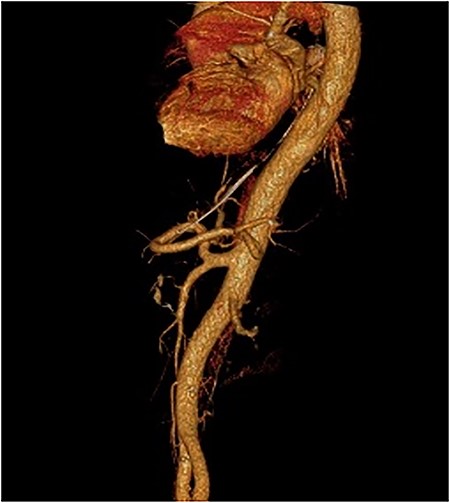

After the negative GI endoscopy for active bleeding, contrast-enhanced CT in the arterial phase was performed and revealed a pseudoaneurysm of the gastroduodenal artery with a diameter of 9 mm, and a second smaller pseudoaneurysm of a branch of gastroduodenal artery were demonstrating (Fig. 4). Furthermore, celiac-mesenteric trunk and worsening image of pancreatitis were depicted (Fig. 5). After that, emergency embolization of the pseudoaneurysms was performed, using a 4-F arterial sheath via the Seldinger technique. A celiac angiogram was obtained with a 4-F angiographic catheter type Cobra (Medical Materials, Boynton Beach, Florida, USA). Using microcatheter Asahi Caravel (Asahi-Intecc USA Medical, Tustin, California, USA), microcatheter SwiftNinja (Merit Medical, South Jordan, Utah, USA) and microcoils of (Boston Scientific, Marlborough, Massachusetts, USA) 2.5 and 3 mm, complete embolization of the two pseudoaneurysms was achieved (Fig. 6).

Contrast-enhanced CT in arterial phase. A pseudoaneurysm of gastroduodenal artery with a diameter of 9 mm (white arrow). B. Smaller pseudoaneurysm of a branch of gastroduodenal artery (white arrow).

Digital subtraction angiography. A. Pseudoaneurysm of gastroduodenal artery (arrow) and a branch of it (arrow head). B. Postembolization images showing absence of blood flow into the pseudoaneurysms.